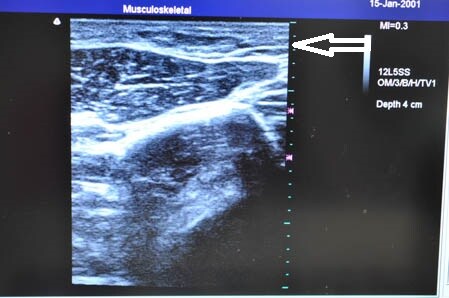

右ちからこぶ。 ↓ ↓ ↓

↓ ↓ ↓